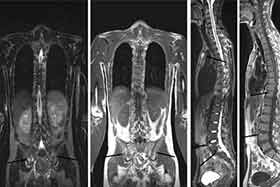

X线片检查分析:患者骶髂关节骨质受损,关节间隙可见狭窄,关节边缘毛糙。脊柱有两处关节变形迹象。

(图:入院时X片显示,骶髂关节受损、脊柱变形)●医生联合会诊分析:

经过三个疗程的个体化治疗后,患者骶髂及颈椎关节无疼痛现象,晨僵消失,X片显示患者脊柱关节已无变形迹象,全身各关节可自由活动。●患者临床治疗结果: